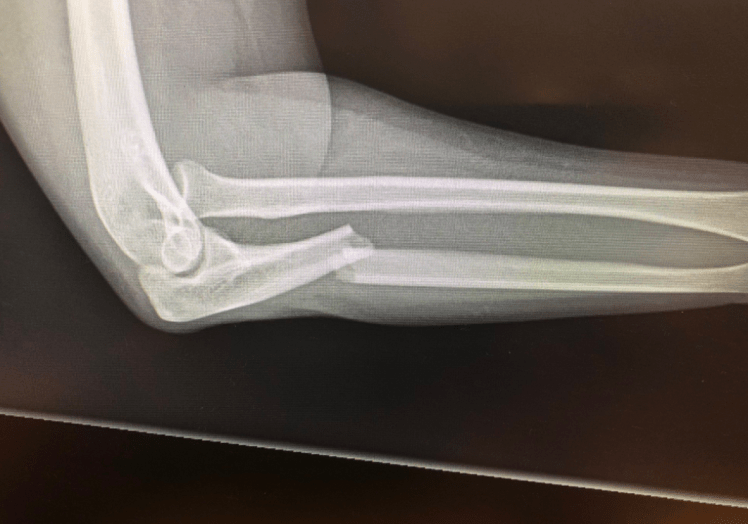

What’s the diagnosis? Gepost op 28 juli 201828 juli 2018 door netwerkvsseh What’s the diagnosis? @emdaily.cooperhealth.org Dit delen: Delen op X (Opent in een nieuw venster) X Share op Facebook (Opent in een nieuw venster) Facebook Delen op LinkedIn (Opent in een nieuw venster) LinkedIn E-mail een link naar een vriend (Opent in een nieuw venster) E-mail Afdrukken (Opent in een nieuw venster) Print Vind-ik-leuk Aan het laden... Gerelateerd